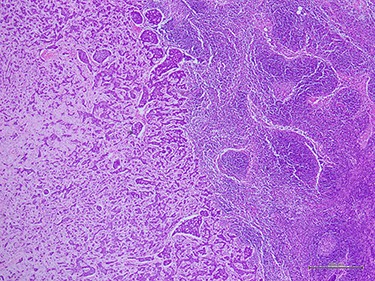

Histologic examination demonstrated metastatic ACC to axillary lymph node (40×).

complex. The left axillary lymph node was found to measure 1 cm after palpation. A mammogram revealed an ill-defined mass at sub-areolar on left breast with angulation 2.3 × 1.9 cm, without suspicious microcalcification or architectural distortion (Fig. 1). Core needle biopsy revealed invasive ductal carcinoma (IDC). Immunohistochemical study (IHC) showed Estrogen receptor (ER), Progesterone receptor (PR), and Human epidermal growth factor receptor 2 (HER2) negative. Fine needle aspiration of left axillary lymph node revealed poorly differentiated metastatic lymph nodes. Metastatic workups were unremarkable. Left lumpectomy and axillary lymph nodes dissection were performed. The final pathology reported ACC measuring 3.5 cm in greatest dimension, lymphovascular invasion, presenting with DCIS, comedonecrosis type, high grade nuclei, microcalcification, all margins are negative for malignancy (Fig. 2). IHC showed CD117 and CK7 positive for malignant ductal cell of tumor, CK5/6 and p63 positive for myoepithelial cells within the tumor. ER, PR and HER-2 were negative. Ki-67 was strongly positive 3 + of nuclear staining, 30% of neoplastic cells (Fig. 3). One of 21 lymph nodes demonstrated metastatic ACC with extranodal extension (Fig. 4). Metastatic part is 0.9 cm in greatest dimension. Postoperative adjuvant chemoradiotherapy was given.